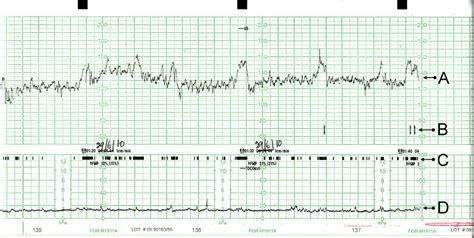

Ein CTG-Gerät zeichnet zwei Hauptkurven auf, die entweder auf Millimeterpapier oder einem digitalen Bildschirm dargestellt werden. Diese Kurven ermöglichen eine kontinuierliche Überwachung des Wohlbefindens des Fötus:

- Obere Kurve: Zeigt die fetale Herzfrequenz (FHF) in Schlägen pro Minute (bpm) an. Diese Kurve schwankt je nach Herzaktivität des Fötus.

- Untere Kurve: Zeichnet die Wehentätigkeit auf. Diese wird entweder durch einen externen Drucksensor auf dem Bauch der Mutter oder durch einen internen Druckkatheter direkt in der Gebärmutter gemessen. Sie zeigt die Kontraktionen des Uterus, deren Stärke in mmHg oder als relative Einheit dargestellt wird.

Die fetale Herzfrequenz eines gesunden Kindes liegt in der Regel zwischen 110 und 160 bpm. Muster wie Akzelerationen (vorübergehende Erhöhungen der FHF) und Dekelerationen (vorübergehende Abnahmen der FHF) geben Hinweise auf die Reaktion des Fötus auf Wehen oder Stressfaktoren. Die Variabilität oder Oszillation der Kurve, also die Fluktuation der Herzfrequenz um einen Mittelwert, liefert wichtige Informationen über den Zustand des autonomen Nervensystems des Fötus.

Die untere Kurve gibt Aufschluss über die Häufigkeit, Dauer und Stärke der Wehen. Regelmäßige und starke Kontraktionen sind ein Zeichen für den Fortschritt der Geburt.